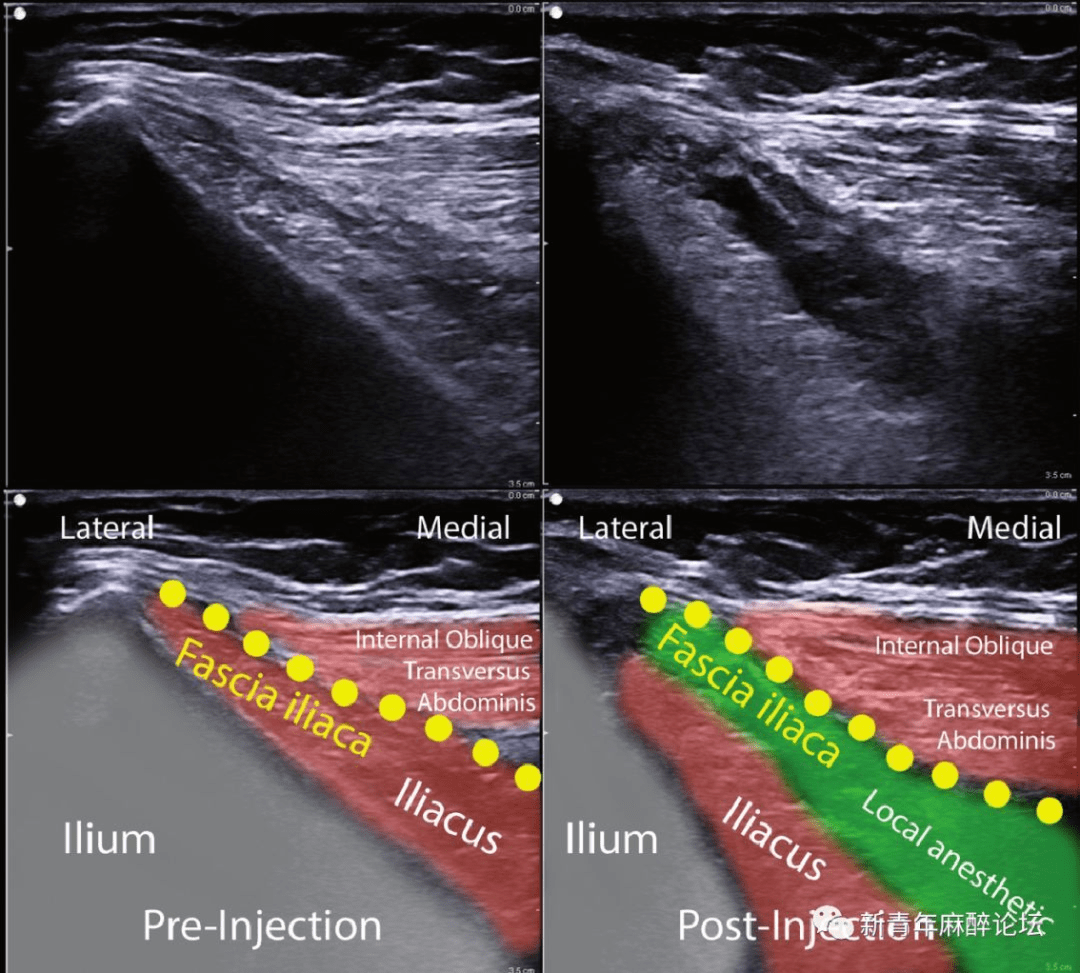

超声下腰丛神经阻滞的解剖要点

高度位于l2,l3水平.注意横突可阻碍腰丛的超声显示(图7).